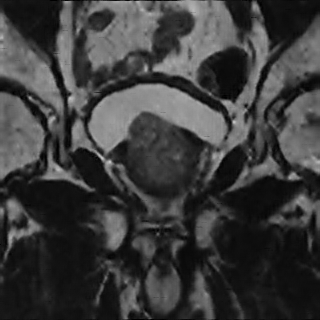

Refer to caption

(a) Bicubic interpolation

(b) Sparse Representation

(c) SRCNN

(d) SRResNet

(e) SRGAN 4x

(f) HR ground truth image

Figure 4: SR result for 4×4\times upscaling using- Bicubic interpolation, SRCNN, Sparse Representation, SRRestNet, and SRGAN

V-C Qualitative SRGAN Image Quality Assessment

Fig. 4 contains an example SR output for each method and the LR and HR images for reference. The LR image is severely pixelated and has no edge fidelity. While the image produced via bicubic interpolation has no pixelation, this method is still unable to preserve the high frequency information found in the ground truth image. The Sparse Representation method produces slightly better results than the previously discussed methods. However, the large amount of space and time overhead required by this model precludes it from clinical use. The SRCNN begins to show edge preservation, however the features within different regions of the output SR image are smoothed out. The SRCNN is especially biased toward smoothing the image because the network only uses MSE loss. The SRResNet has both MSE and perceptual loss yet fails to outperform the SRGAN. Clearly, the discriminator network seeks out the high frequency information that differentiates HR and LR images, thus forcing the SRGAN output to have far more high frequency details than the output of the SRResNet. The SRGAN 8x network is not able to maintain as high an edge fidelity as the SRGAN 4x network. This result is expected because the SRGAN 8x network is provided with far less information since the input LR image is a further 2x smaller in both dimensions (Fig. 5). Overall, in comparing the SRGAN to the other models, the outputs from the SRGAN are visually closer to the original HR ground truth images.